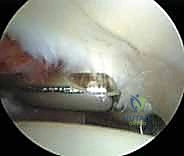

3. الجولة التشخيصية داخل المفصل (Diagnostic Arthroscopy)

بمجرد دخول الكاميرا، يتم عرض صورة مكبرة وعالية الدقة (4K) لداخل المفصل على شاشة كبيرة. يقوم الدكتور هطيف بفحص جميع الهياكل بدقة متناهية: الغضروف المفصلي، الشفا الحقي، الرباط المدور، والبحث عن أي التهابات أو أجسام سائبة. يتم استخدام سائل ملحي معقم لضخ المفصل، مما يوسع المساحة ويغسل الدم لضمان رؤية واضحة تماماً.

* إصلاح الشفا الحقي (Labral Repair): إذا كان الشفا ممزقاً ولكن نسيجه لا يزال جيداً، يتم إعادة تثبيته في حافة الحُق باستخدام خطاطيف صغيرة جداً (Suture Anchors) تزرع في العظم وتمرر خيوطاً قوية لربط النسيج الممزق.